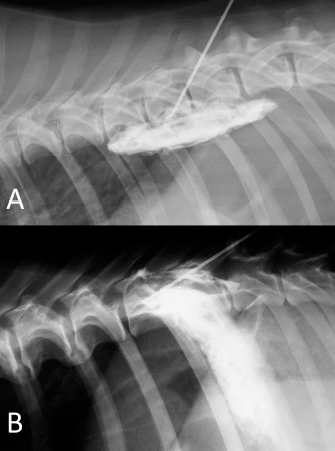

Fig. 6. NMB and ioversol mixed longitudinal and cloud-like (A) and intercostal (B) spread pattern in a lateral radiograph of a dog cadaver.

Although with some minor intra- and inter-specific differences, a positive air-LOR test was associated with longitudinal spread along the extrapleural compartment of the TPVS in 100% of the animals. In dog cadavers, the median injected volume (ml kg−1) of the mixture was 0.6 ml (0.22–1.25). The lateral thoracic radiographs showed multi-segmental spread in 100% of the subjects, with a median of 4.5 (2–10) vertebrae and a distribution of 2.5 (0–7) vertebra cranial and 1.0 (0–3) vertebra caudal to the injection level. A longitudinal spread pattern was noted on all radiographs, mixed with a cloudy pattern in 11/14 (78%) images and with an intercostal pattern at the level of the ninth intercostal space in 1/14 (7%) image (Fig. 6). Necropsy revealed multi-segmental ipsilateral longitudinal spread in 100% of the subjects (Fig. 7). The median stained intercostal spaces were 6.5 (4–11), with 5 or more spaces stained in 78%, whereas contralateral longitudinal spread was detected in 9/14 (64.3%) spaces, with a median of 2.5 (0–6) (Fig. 8). The median cranial versus caudal spread ipsilateral and contralateral to the injection site was 3 (1–7) versus 2 (0–3) and 0 (0–4) versus 1 (0–2) space, respectively. Distributions of NMB and ioversol after each mixture injection are shown in Figure 9. The only statistically significant correlation was between the radiographical and the necroscopic assessment of the longitudinal spread in the dog cadavers ( p=0.0028).

In cat cadavers, the median injected volume (ml kg−1) was 0.84 ml (0.6–1.5). The lateral thoracic radiographs disclosed multi-segmental spread in all of the subjects, with a median of 5 (2–6) vertebrae and distribution of 2 (0–3) vertebrae cranial and 2 (1–2) vertebrae caudal to the injection level. A mix of cloudy and linear spread patterns was noted on all radiographs, with the concurrent presence of an intercostal pattern at the level of the ninth intercostal space in 1/6 (17%) image (Fig. 10). Necropsy revealed multi-segmental ipsilateral longitudinal spread in 100% of the subjects. The median number of stained intercostal spaces (dorsal aspect) was 6.5 (5–7), with 5 or more spaces stained in all subjects, whereas contralateral longitudinal spread was seen in 5/6 (83.3%) subjects, with a median of 5 (0–7) (Fig. 11). The median distribution of the cranial vs. caudal spread ipsilateral and contralateral to the injection site was 3 (2–4) versus 2.5 (1–3) spaces and 2 (0–4) versus 2 (0–3) spaces, respectively. Staining of the parietal pleura surrounding the dorsal mediastinum, the so called pre-vertebral space and the proximal intercostal spaces were observed in all subjects, regardless of the volume or the spread pattern. Distributions of NMB and ioversol after each mixture injection are shown in Figure 12.